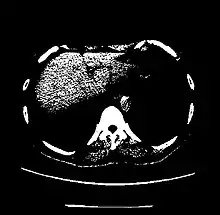

The Hounsfield scale (/ˈhaʊnzfiːld/ HOWNZ-feeld), named after Sir Godfrey Hounsfield, is a quantitative scale for describing radiodensity. It is frequently used in CT scans, where its value is also termed CT number.

| Kidney | +20 to +45[5] | |

| Liver | 60 ± 6[23] | |

A practical application of this is in evaluation of tumors, where, for example, an adrenal tumor with a radiodensity of less than 10 HU is rather fatty in composition and almost certainly a benign adrenal adenoma.[28]